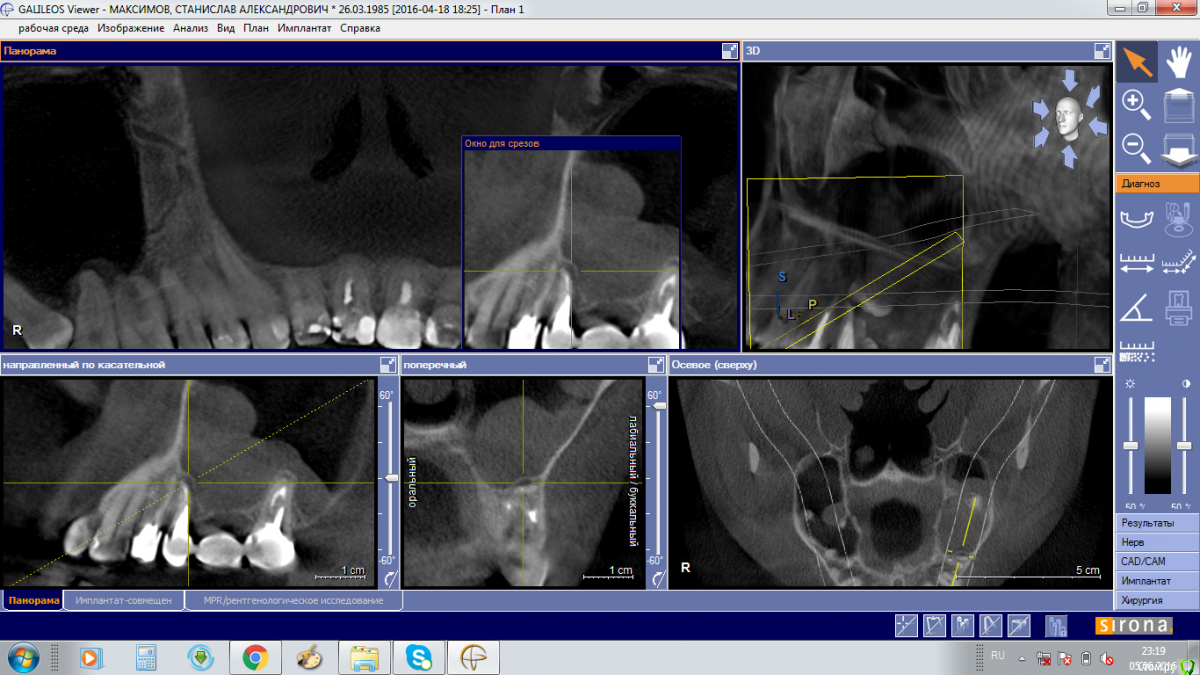

Stanis777 Опубликовано 6 июня, 2016 Поделиться Опубликовано 6 июня, 2016 Здравствуйте!Два месяца назад переболел левосторонним гайморитом, температура была до 39, 3 раза делали проколы. ЛОР выразил мнение о связи с зубами. Через 3 дня после пролечивания сделали КЛКТ, по результатам которого ЛОР сказал что в зубах 5 и 7 воспаление и отправил к стоматологу-хирургу. Стоматолог-хирург осмотрев меня и изучив КЛКТ сказал что в пазухе киста, которую нужно удалять эндоскопически и прямой связи с зубами не видит.Сейчас каких-то явных симптомов, кроме ощущения как бы небольшой припухлости левой щеки нет. В прикреплении фото с КЛКТ. Подскажите исходя из фото что нужно делать? Лечить-удалять зубы или киста не связана с ними? И в какое мед.учреждение в Москве лучше обратиться для лечения, желательно по ОМС. Ссылка на комментарий

Bier Опубликовано 6 июня, 2016 Поделиться Опубликовано 6 июня, 2016 проблемы в пазухе одонтогенные. (т.е. от зубов) Ссылка на комментарий

Doctor Vlad Опубликовано 8 июня, 2016 Поделиться Опубликовано 8 июня, 2016 5ка еще одно лечение не переживет Ссылка на комментарий

Bier Опубликовано 8 июня, 2016 Поделиться Опубликовано 8 июня, 2016 перелечить проблемно, скорее всего удаление. Ссылка на комментарий